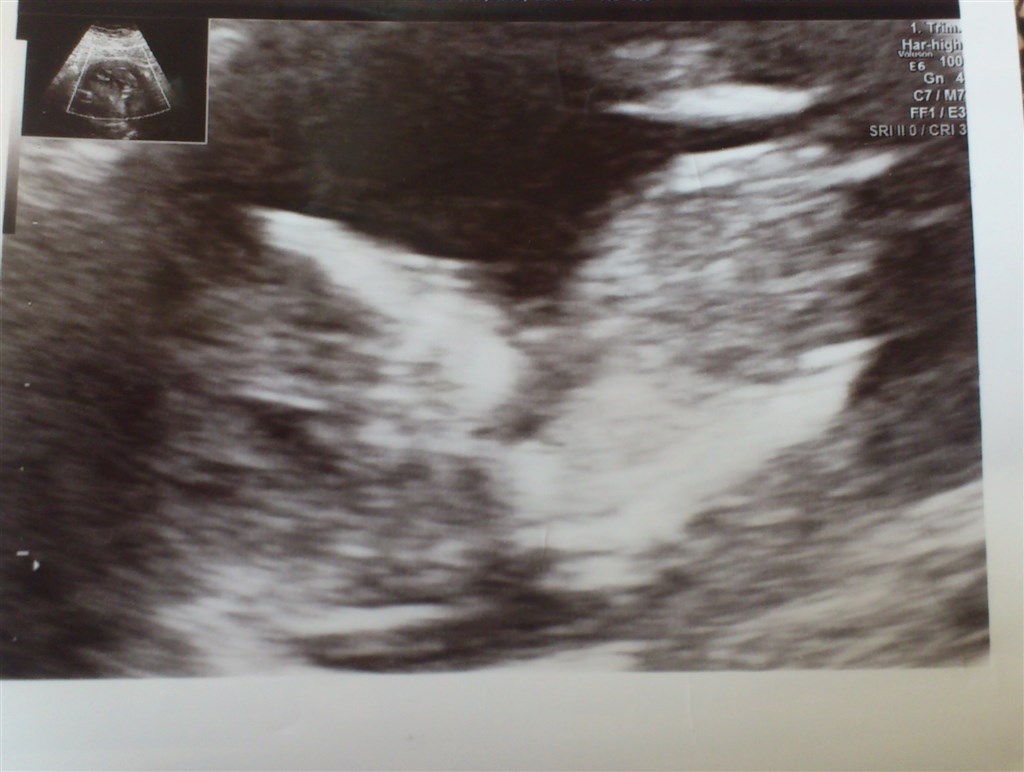

Der lå jo den sødeste lille skumfidus derinde

Den lå forkert og den puttede rigtigt, men da hun så skubbede lidt til den kom der liv i den. Den bevægede arme og ben hver gang hun rykkede på skanneren - den lille lort ville da ikke vækkes

Men alt så fint ud og vi fik tallet 1:19232 - så det kan jo ikke blive bedre

Og nu billeder af den lille skumfidus, som på det ene billede holder armen op foran hovedet for at gemme sig